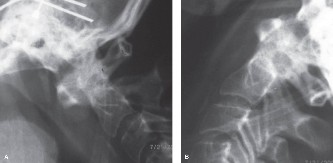

In addition to MRI, a fine-cut computed tomography (CT) scan is essential for evaluating bony destruction. CT allows the surgeon to assess bone stock for pedicle screw purchase and to template the size of the interbody cages required for anterior column reconstruction. Upright standing radiographs (if the patient can tolerate them) or full-length supine films are necessary to evaluate global spinal alignment and regional kyphosis.

Phase 3: Long-Term Follow-Up and Functional Restoration (Months 3–12)

Upon completion of the 12-week antibiotic course, a final set of inflammatory markers is drawn. Advanced imaging (MRI or CT) is generally not required at the end of treatment if the patient is asymptomatic and markers are normal, as MRI can show persistent marrow edema for many months despite microbiological cure. Radiographs are obtained to assess for spontaneous fusion or the integrity of surgical hardware. The patient is advanced to an unrestricted, progressive resistance training program to rebuild paraspinal musculature and improve cardiovascular endurance.